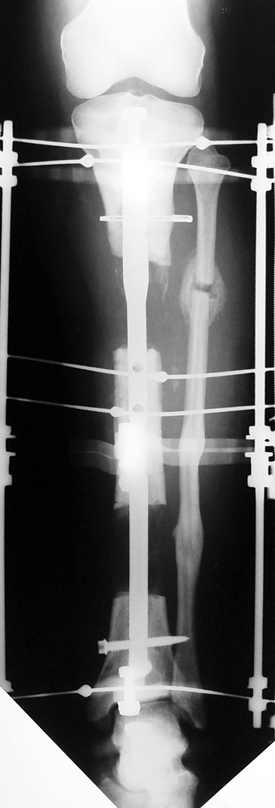

Appropriate radical debridement necessitates excision of all necrotic bone and soft tissues, and frequently causes instability at the involved extremity. The remaining bone and soft tissue defect has to be fixed and reconstructed. The distraction osteogenesis method of Ilizarov is used successfully for achievement of union, correction of the deformity, elimination of limb length inequality and reconstruction of segmental bone defects.

The duration of external fixation (external fixation index) depends on the amount of distraction required, and the extremity is prone to complications during this period. After the distraction phase is completed, the external fixator remains in place during the consolidation phase, which lasts twice as long as the distraction phase; but this period is hardly tolerated. If the external fixator is removed before sufficient consolidation is achieved, fractures, deformity and shortness will be the result. In our department, ‘lenghthening over nail’ method is used in order to decrease the external fixation index and increase patient comfort and activity level. In this method, the intramedullary nail is statically locked after the completion of the distraction phase, and external fixator is removed. The extremity is stabilized by the intramedullary nail during consolidation phase. In this way, complications due to long external fixation index or early removal of the external fixator are avoided.